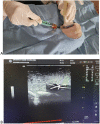

Ultrasound-guided vascular access is a medical procedure that is becoming increasingly common in daily practice and is recommended to avoid iatrogenic complications. One of the procedures with a high-risk rate of complications is the vascular puncture. However, training on this technique can be challenging due to the limited availability of simulation models. We propose a simple, cost-effective, and effective ultrasound-guided vascular access simulation model that utilizes chicken breast and a urine catheter to address this need.